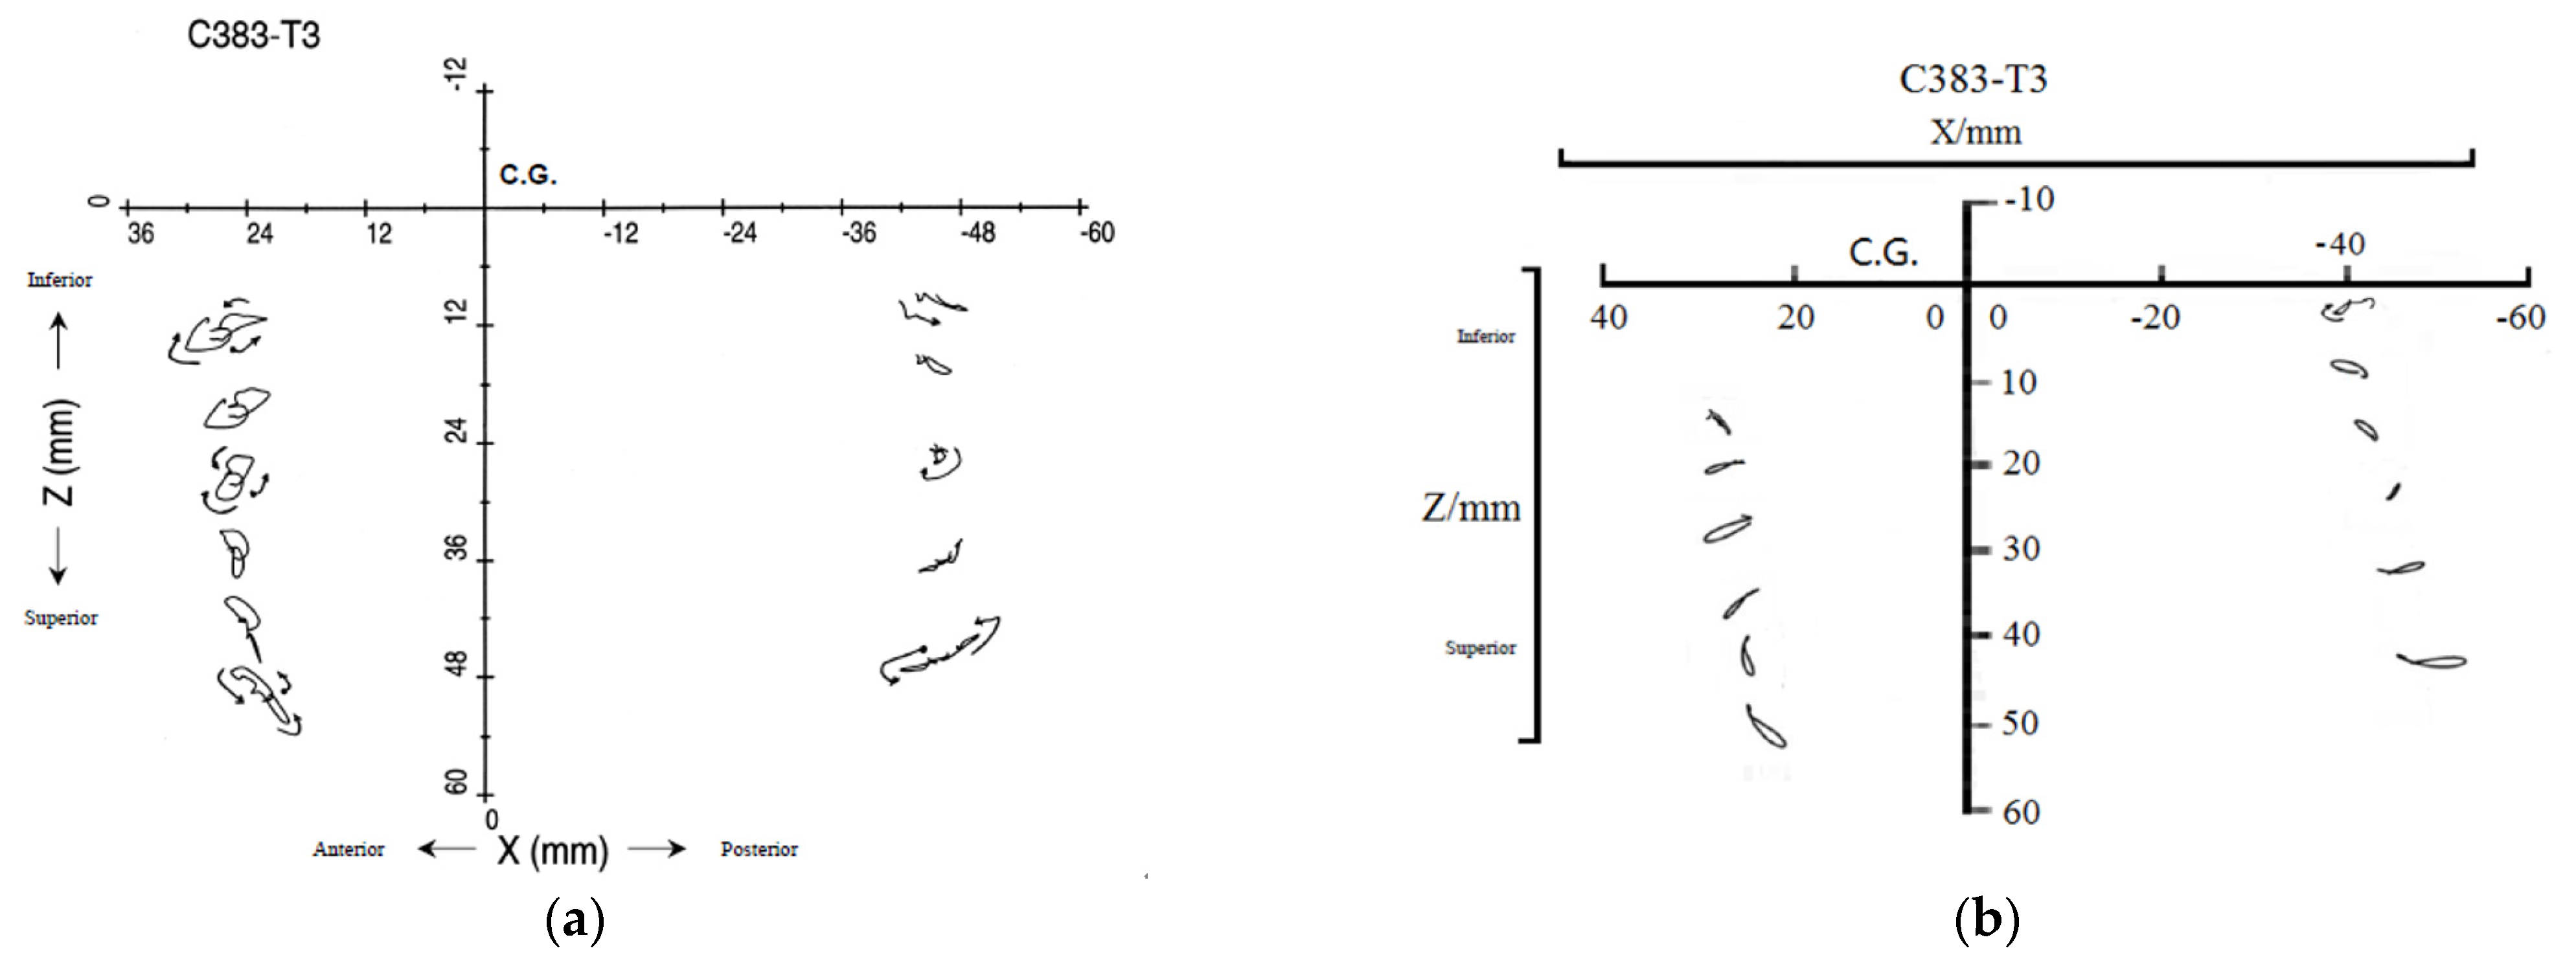

2.1.4. Experimental Validation of Hardy’s Craniocerebral Relative Displacement